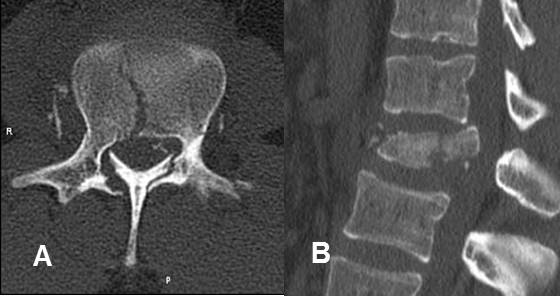

Fig 182. Fractura de Chance.

Fractura transversa y no desplazada, en el cuerpo vertebral y los elementos posteriores.